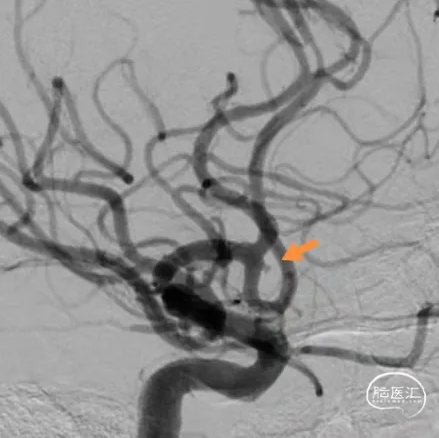

术前影像

栓塞过程

栓塞微导管精准塑形后,前推顺利到位,依次填塞三枚Jasper®SS弹簧圈。瘤颈处有壶腹,为增加弹簧圈稳定性,降低动脉瘤复发率,释放支架,复查造影,动脉瘤填塞致密,载瘤动脉通畅良好。

术后即刻影像